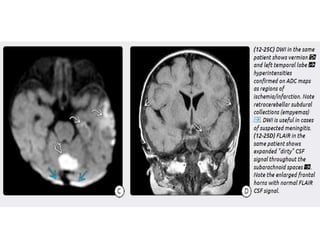

Imaging in CNS Infections